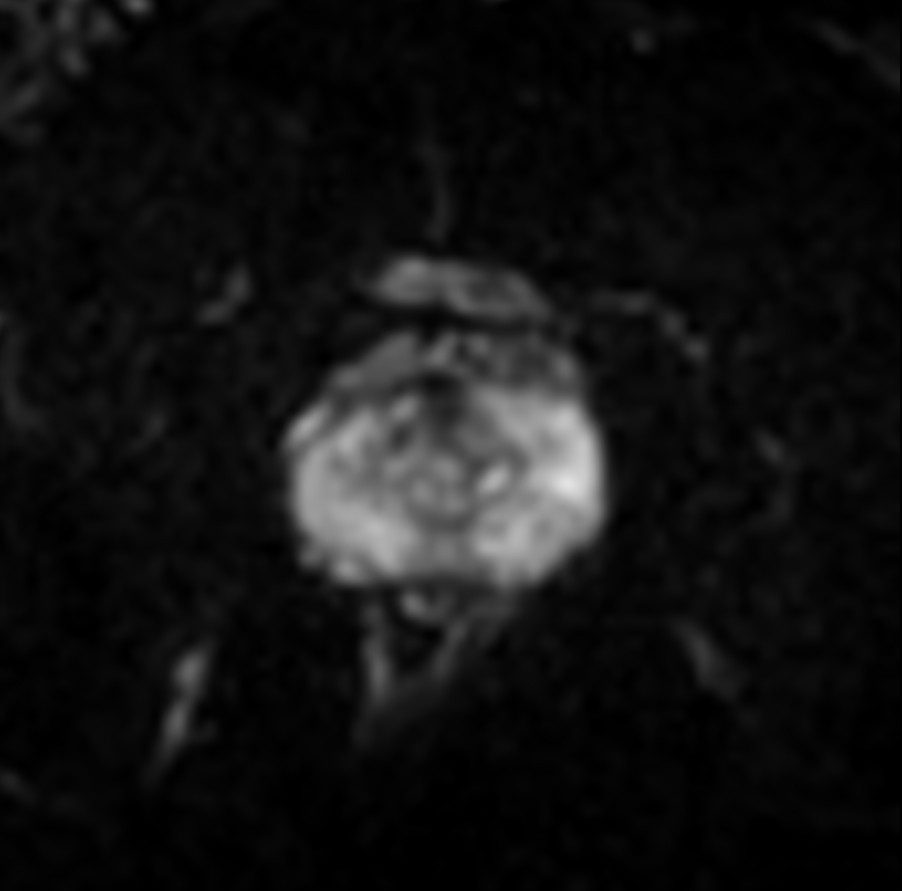

Prostate with dS ZOOM imaging

Aarhus University Hospital, Denmark